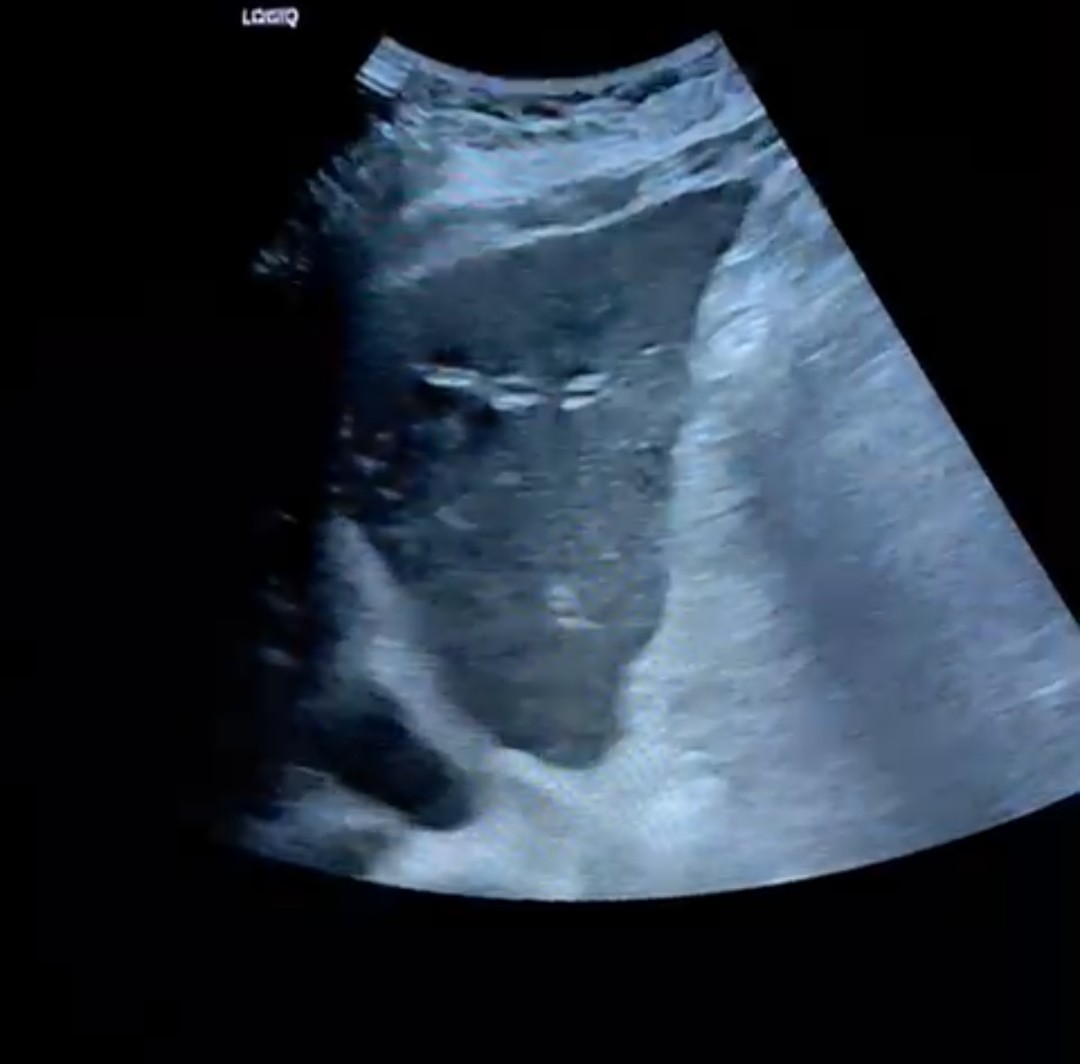

La paciente acude tras una semana de tratamiento antibiótico con cultivo de orina negativo. Persiste febrícula y molestias en hipocondrio derecho. Realizamos ecografía clínica donde se observa lesiones compatibles con metástasis. Se decide ingreso para estudio. Tras TAC de abdomen, TAC de tórax y colonoscopia no se observa tumor primario. Se decide una colangio-RM donde se observa tumoración quística en páncreas con anatomía patológica compatible con adenocarcinoma mucinoso de alto grado en páncreas.

Es importante el diagnóstico diferencial de la fiebre sin foco, no pudiendo descartar además de los procesos infecciosos, los oncológicos, debiendo preguntar por síntomas constitucionales. En este caso la ecografía clínica abdominal dio con la clave del diagnóstico.